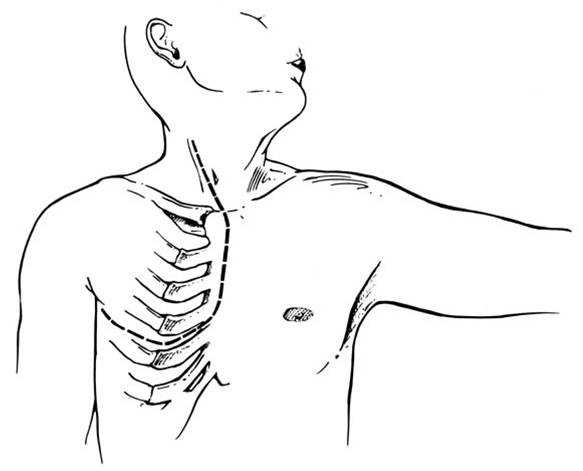

Any anterior mediastinal mass (Figures 1, 2) must be considered suspect for germ cell tumor, especially in a young male. Errors in diagnosis are not uncommon and can result in mismanagement of a potentially curable patient. All patients with an anterior mediastinal mass should have alpha-fetoprotein (AFP), β-human chorionic gonadotropin (β-HCG), and lactate dehydrogenase (LDH) levels drawn at the outset. The different types of germ cell histologies are shown in Figure 3.

Figure 1a: Chest radiograph of mediastinal germ cell tumor

Figure 1b: Chest radiograph of mediastinal germ cell tumor